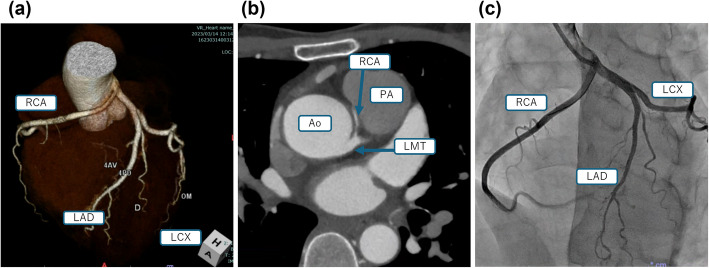

Background: Coronary artery origin anomalies, though often incidentally detected, can lead to sudden death. Comprehensive perioperative management is essential. We report a case of an anomalous right coronary artery (RCA) arising from the left main coronary artery (LMCA) and coursing between the aorta and pulmonary artery, discovered after myocardial infarction, in which intraoperative management ensured successful coronary reconstruction.

Case presentation: A 49-year-old woman presented with chest pain and ST segment elevation. Coronary angiography revealed an anomalous RCA demonstrating compressive ischemia by the aorta and pulmonary artery. Preoperatively, blood pressure was stabilized with an isosorbide dinitrate patch. Under cardiopulmonary bypass, the RCA was transected and reanastomosed to its physiological aortic position. Intraoperatively, nicorandil was administered to suppress vascular smooth muscle contraction, while five-lead ECG, transesophageal echocardiography, and operative ultrasound monitoring enabled early detection of ischemia and prevented hypertension. Postoperative ventricular premature contractions resolved by the next day, with uneventful recovery.